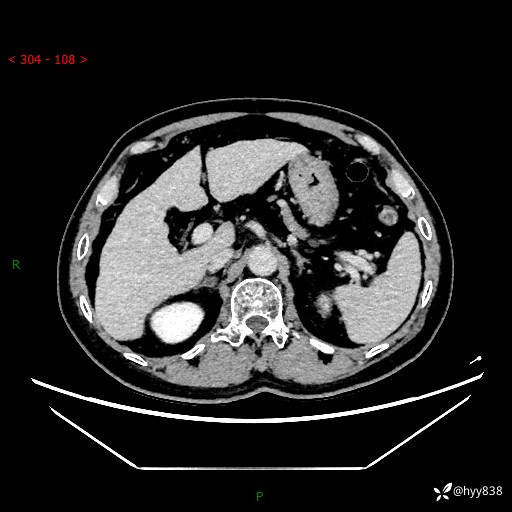

增强动脉期